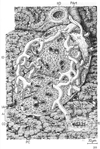

消化器;消化器系【しょうかきけい】(栄養分を取りこむ器官系で、言い換えれば、身体の成長に必要な物質と身体の活動を支えるためのエネルギー源とを取り入れるのが消化器の役割である。消化器は口腔・咽頭・食道・胃・小腸・大腸などから構成された「消化管」とこれに開く唾液腺・肝臓・膵臓などの「消化腺」とから出来ている。)